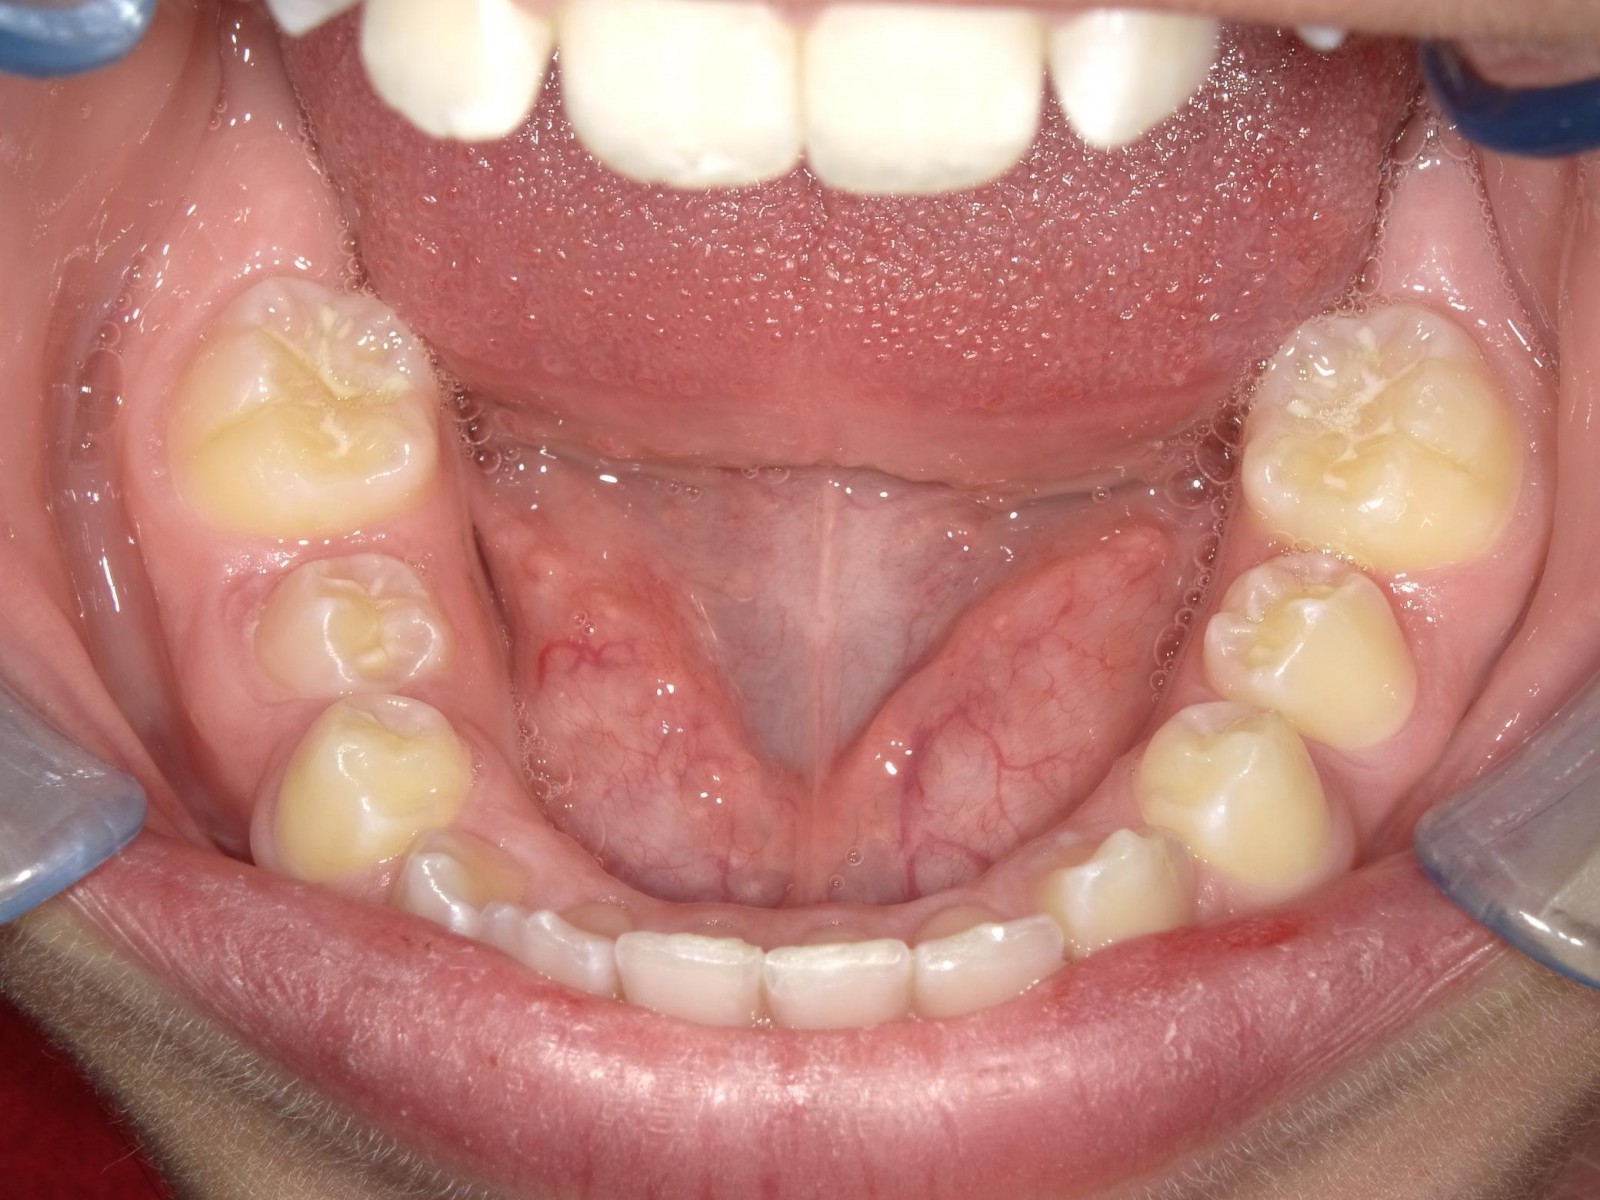

1-26 maand Volledig vast onderkaak + Transforce onderkaak